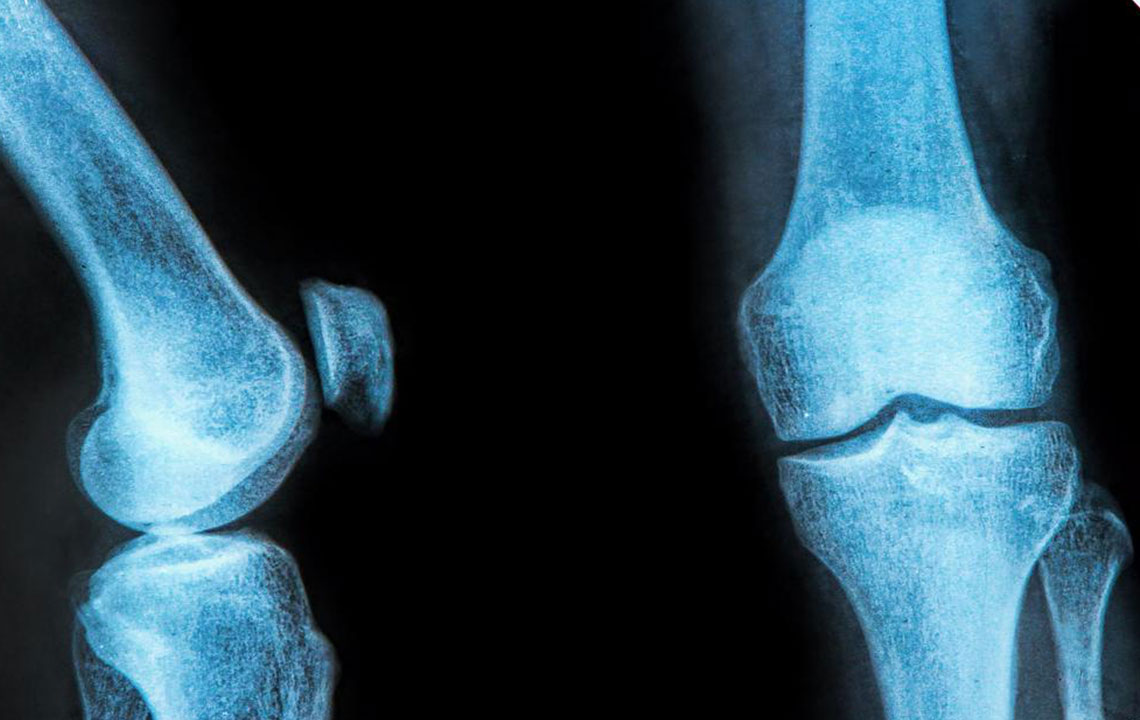

The rubbery C-shaped disc cushioning your knee is a meniscus. There are two menisci in each knee. One at the inner side and the other on the outer side. It is this meniscus that helps to keep your knee steady. It balances your body weight around your knee. If there is a tear in the meniscus, you will experience a lot of pain. It will also prevent the proper functioning of your knee.

A meniscus tear happens when the knee is twisted or turned abruptly while the foot is still flat on the ground. It can occur due to heavy weight lifting or while playing high-impact sports. A brace for meniscus tear can prevent and protect you from further injury.